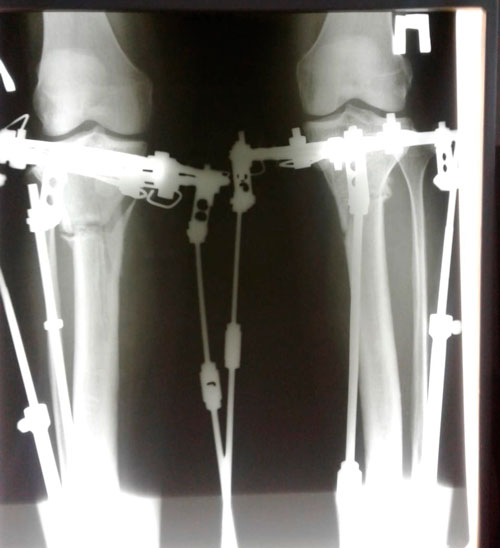

Исходник - 46 лет.

Дата операции 22.06.2018г.

Дата снятия - 02.11.2018г.

Срок сращения - 98 дней.